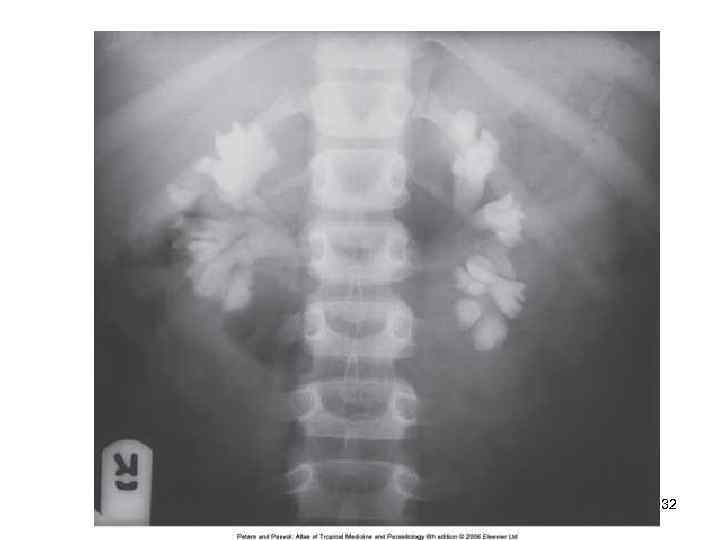

32

Диагностика • Исследование мочи на яйца шистосом после центрифугирования • Максимальное количество яиц выделяется с мочой около 10 -12 часов дня • Интенсивная инвазия оценивается при числе яиц более 50 на 10 мл. мочи • Цистоскопия позволяет выявить изменения на слизистой оболочке мочевого пузыря: гранулемы, » песчаные пятна» . • Эндобиопсия- выявляются яйца S. haematobium • Обзорная рентгенография –обнаруживается обызвествление стенок мочевого пузыря Контрастная урография -изменение структуры мочеточников 33